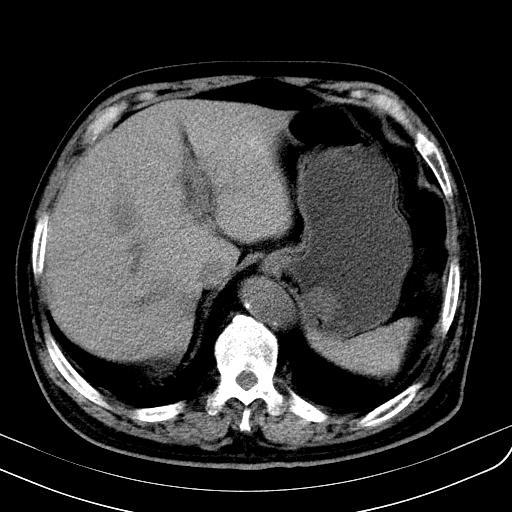

胃底靠近胃大弯处可见一圆形软组织影,直径为3.45cm,ct值约为30.1hu

胃底间质瘤

考虑为胃底间质瘤

胃底良性肿瘤,考虑间质瘤

边缘光滑,密度均匀,良性占位,首先考虑平滑肌瘤。